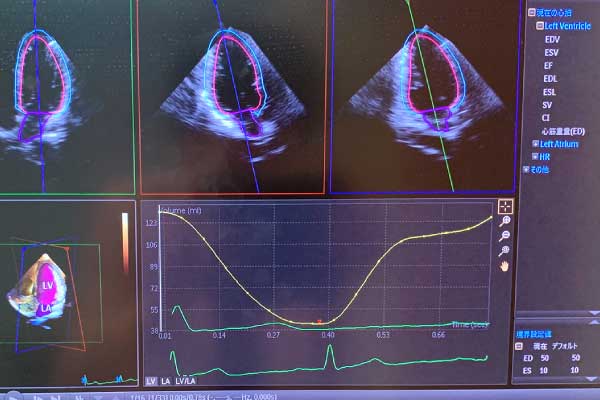

心臓超音波検査部門は、田邊教授の指導のもと、3次元エコーや心筋ストレイン等の新しい技術や日々進歩する装置を常に取り入れながら、心臓疾患に困っている患者様のために医局員が、日夜問わず心エコーに取り組んでおります。

田邊教授は心臓超音波を用いた研究を長年のテーマとしており、現在は高齢者弁膜疾患、負荷心エコー、心不全における心エコー等に関する研究を主に行っています。